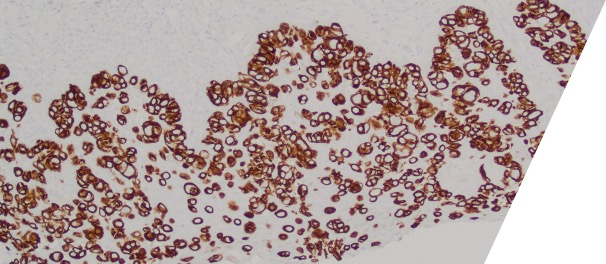

Large round malignant cells with pale cytoplasm and enlarged nucleolus and prominent nucleoli are present within the epidermis. The cytoplasm contains mucin. Differential diagnosis include HSIL, Paget disease (primary or secondary), and melanoma in situ. The lesional cells are strongly positive for CK7, CK20, CAM5.2 and GATA3, scattered positive for p63; and patchy staining for p16, negative for ER and SOX10. High-risk HPV-ISH is negative.

Patient's history of invasive high-grade urothelial carcinoma is shown. The tumor cells showed similar morphological features to the tumor cells in current specimen. The findings are compatible with secondary involvement by previously diagnosed urothelial carcinoma.

Due to morphological similarity both architecturally and cytologically, precise diagnosis based on H&E alone can be challenging, and IHC can be overlap. The current case highlight the importance of clinical history in establishing an accurate diagnosis for patients with an extension of urothelial carcinoma into the GYN tract.